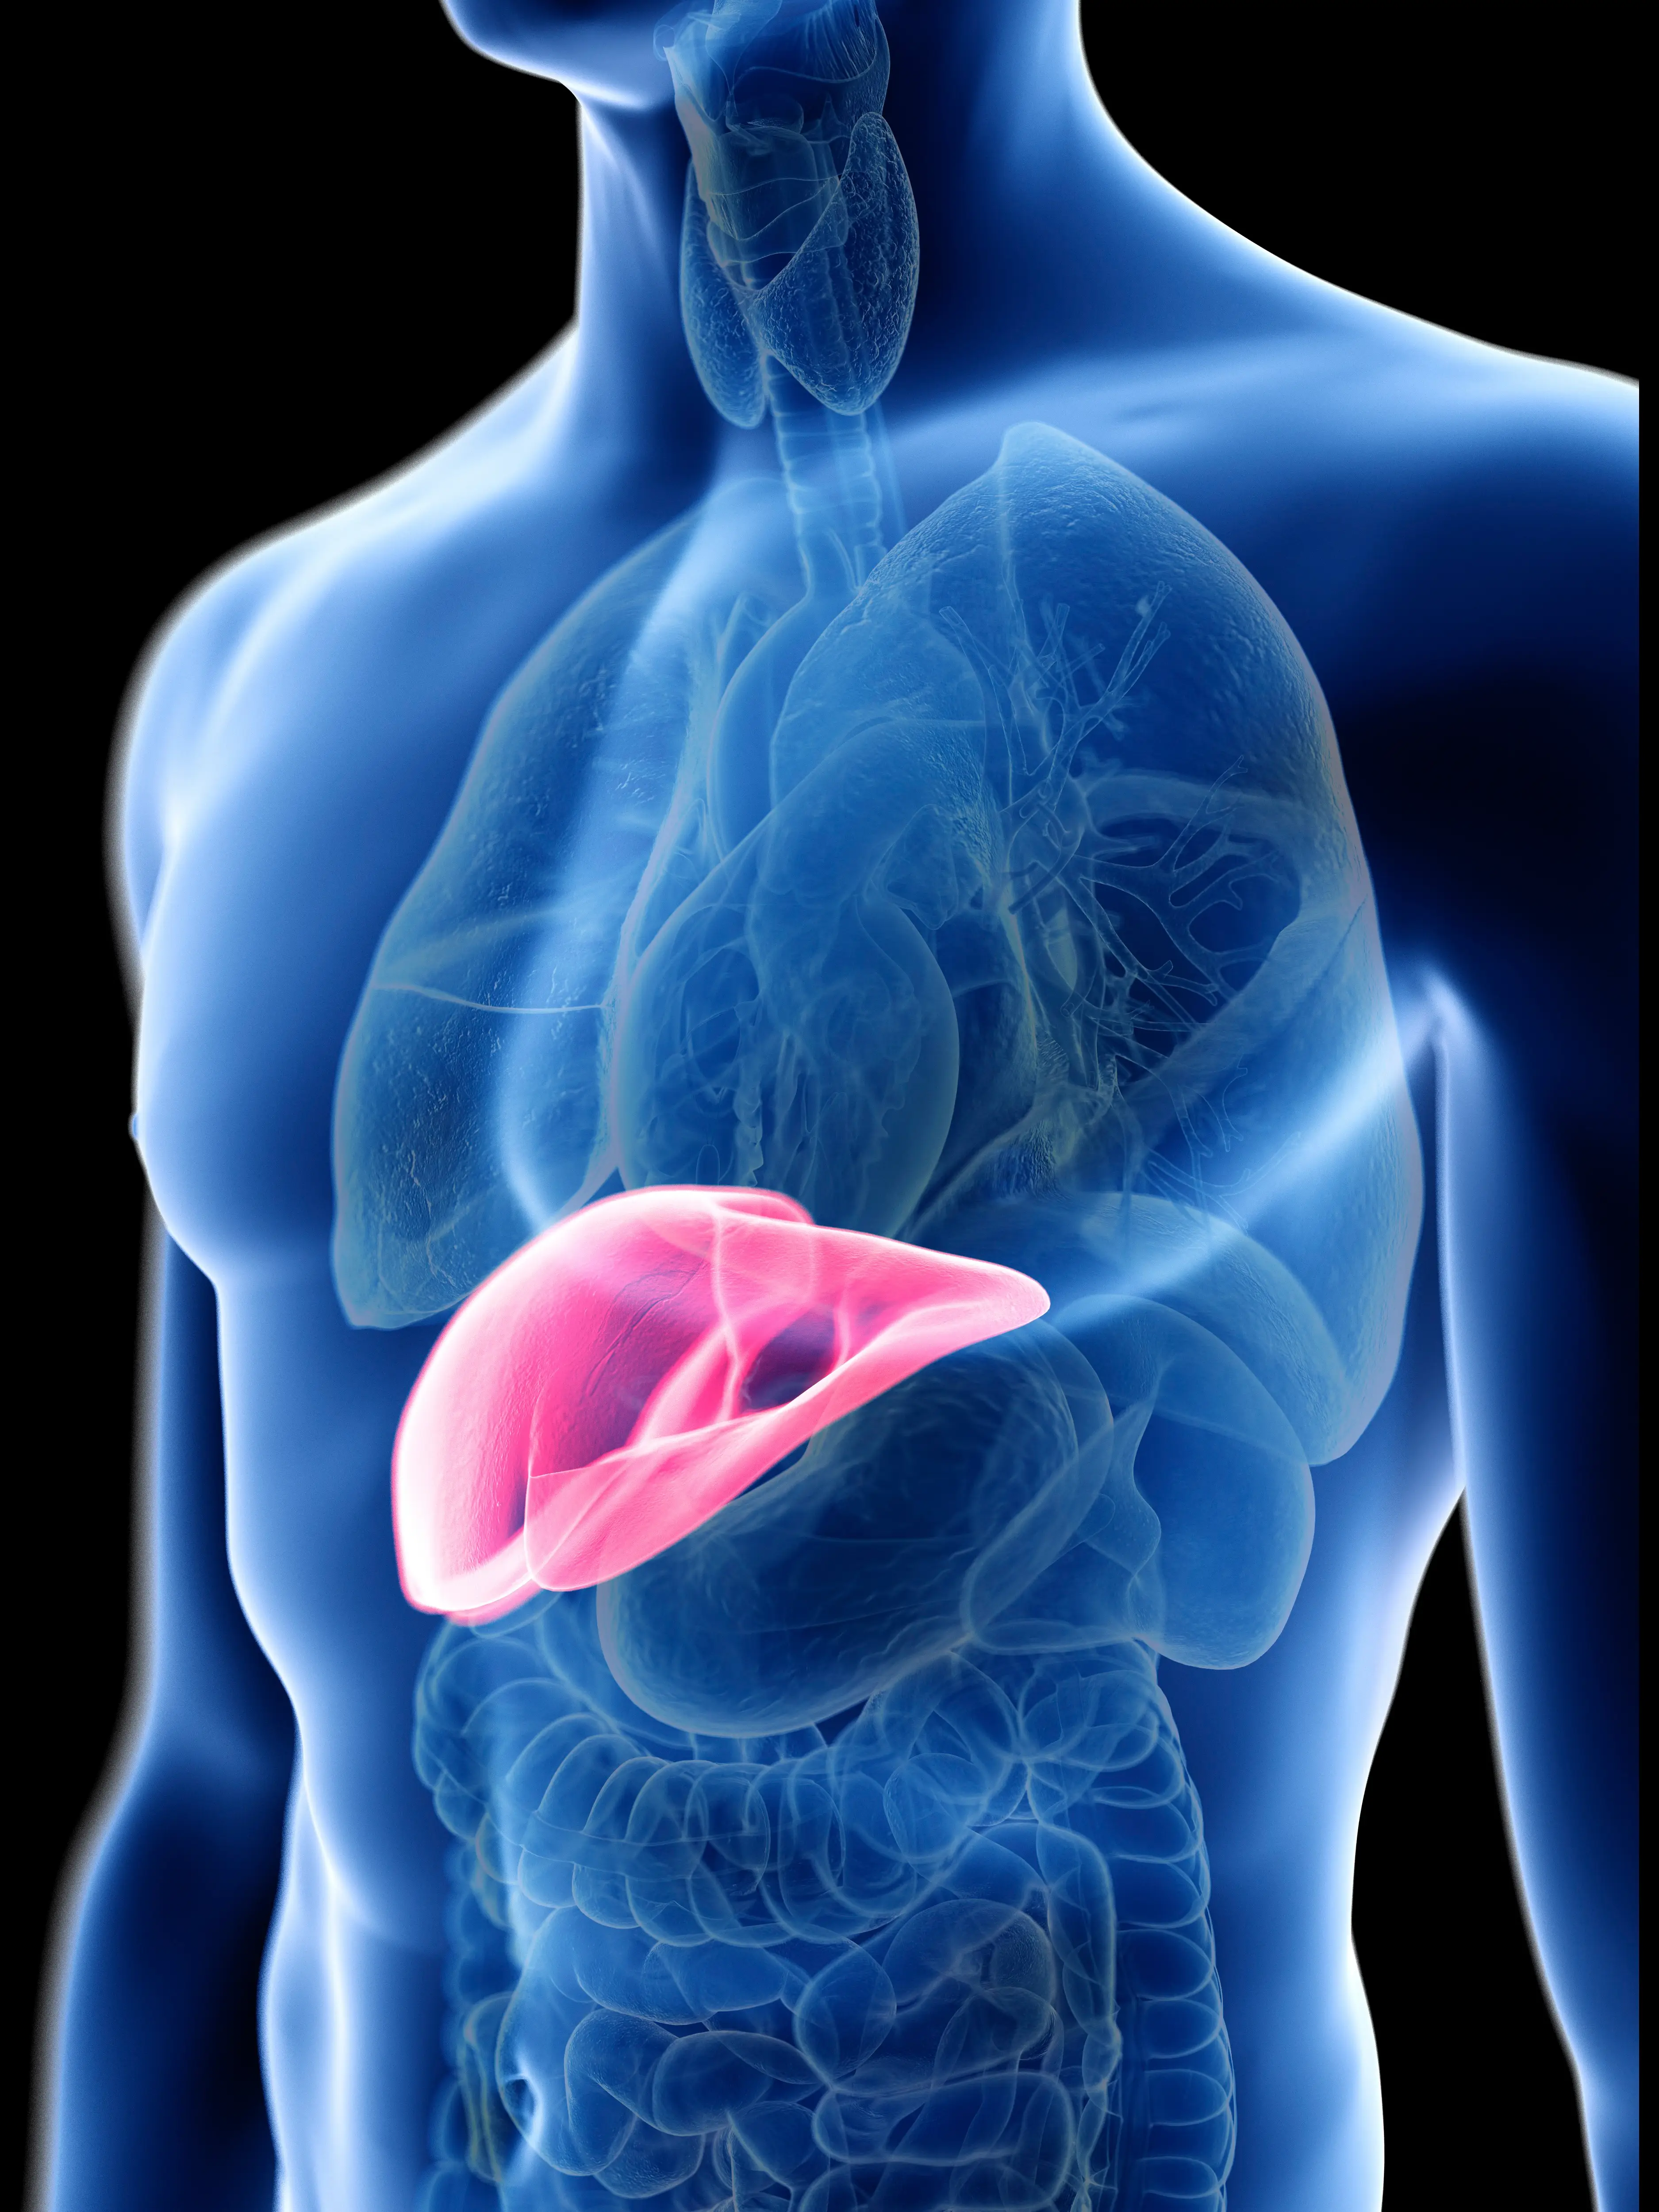

His reasoning stemmed from the fact that these vitamins can become stockpiled in a consumer’s liver and trigger issues when it comes to this vital organ, and could see its surrounding fatty tissue rise to toxic levels.

In these cases, liver injury is possible, along with the development of lung cancer later down the line.